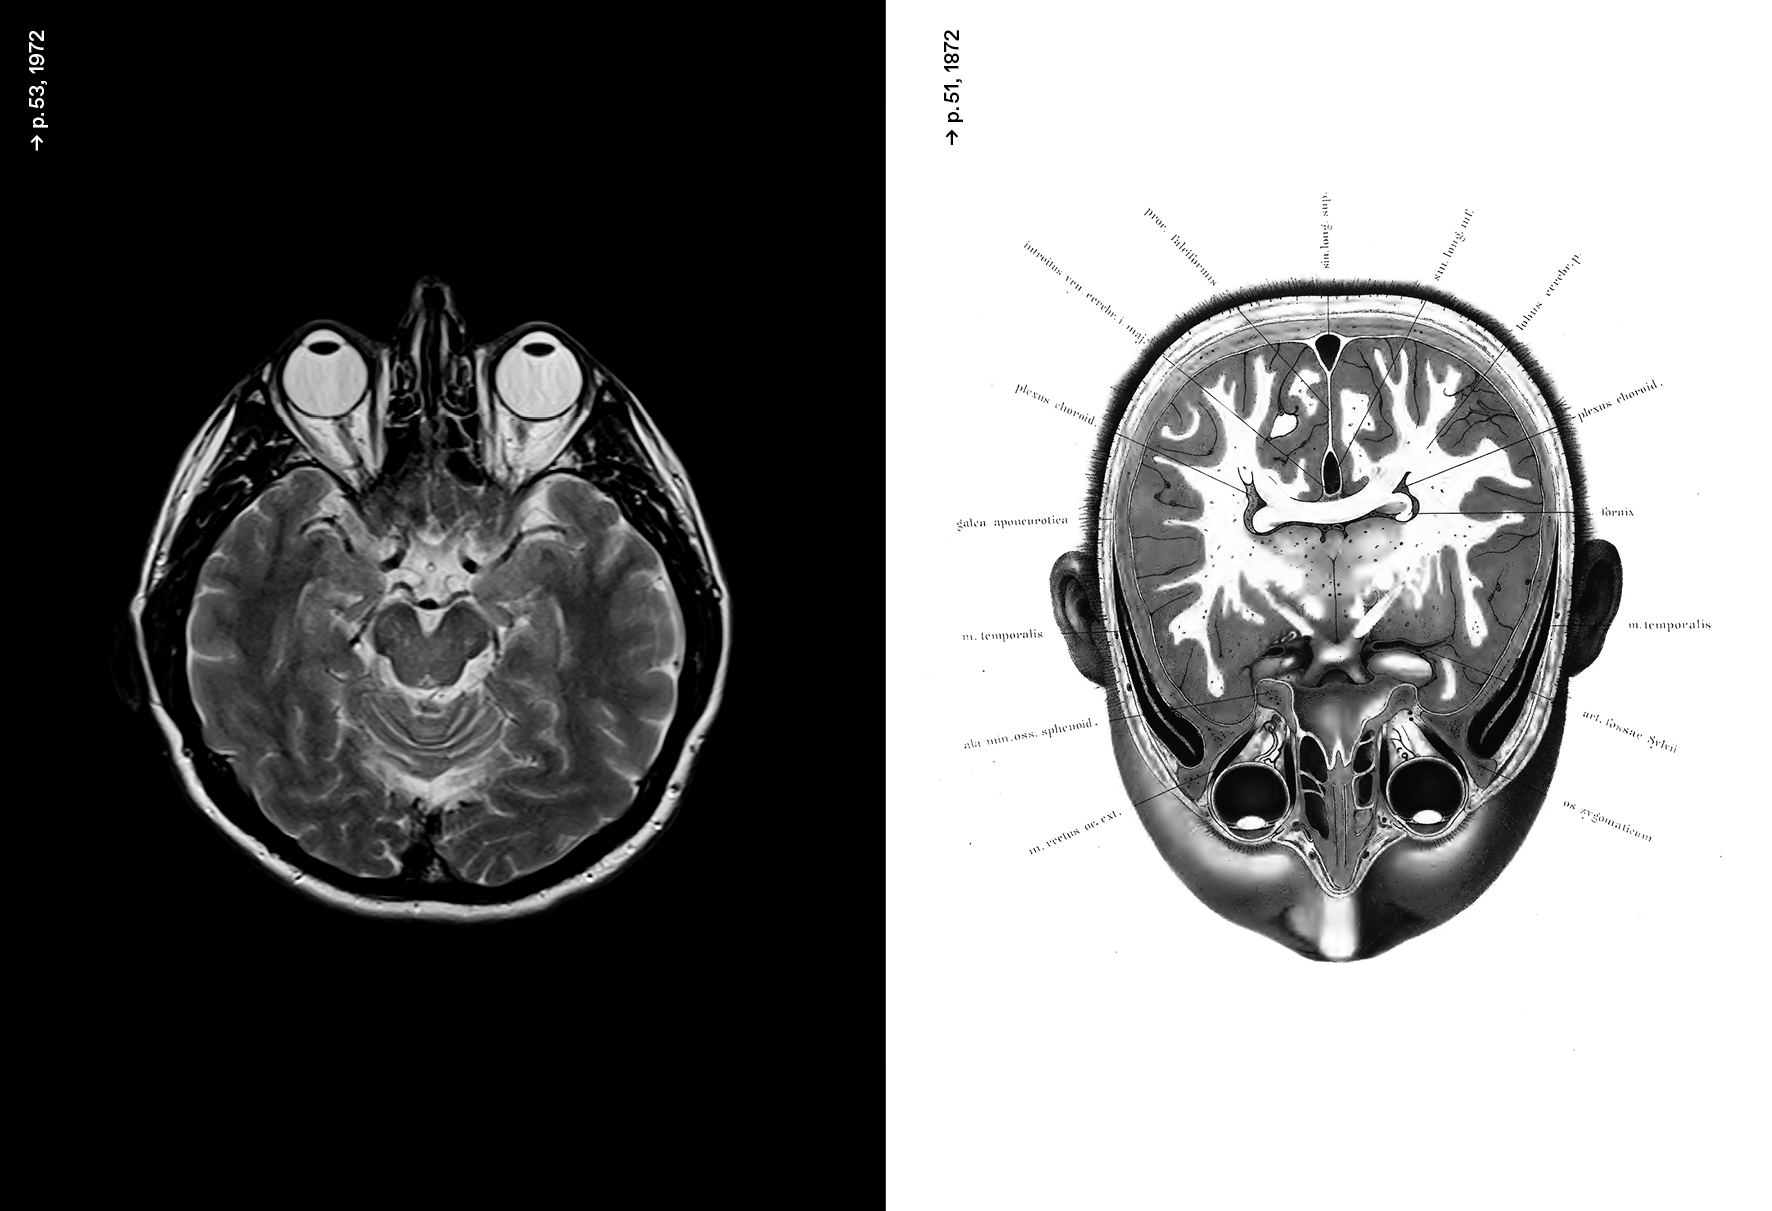

Deep learning, machine learning, algorithme, réseau de neurones, data mining... L’intelligence artificielle ou la capacité à simuler l'intelligence humaine a investi aujourd'hui presque tous les domaines de notre société. Pourtant son histoire est peu connue. En croisant celle des neurosciences et de la neuro-computation avec l'histoire de l'art, la publication "Neurones, les intelligences simulées" dévoile un récit singulier, entre recherche et création. Ouvrage sous la direction de Frédéric Migayrou et Camille Lenglois.

Les notions de « deep learning », de « machine learning » définissent aujourd’hui l’intelligence artificielle (IA) comme un nouveau paradigme établi aussi bien dans le domaine industriel, économique, militaire ou sociopolitique, que dans nos vies quotidiennes. Pourtant cette histoire n’a jamais été véritablement mise en relation avec celle des neurosciences et de la neuro-computation. « Objet cerveau », « Intelligence des jeux », « Cyber-zoo », « Extended Minds », « Deep Learning - Arbres et réseaux neuronaux »... La redéfinition des notions liées à l'IA nous permet de mieux comprendre le développement continu des recherches sur la simulation de l’intelligence humaine et son interaction permanente avec les domaines de la science et de la création.